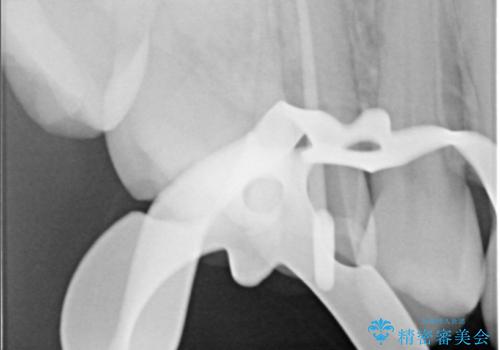

右上5番目の歯が根管治療途中となっており、前医院にて根管が狭く治療が難しいと言われてしまいセカンドオピニオンで当院にいらっしゃいました。

右上5番レントゲン写真上では根管が確認しずらく、根管の狭窄が予想されました。マイクロスコープを使用し、根尖部まで器具を到達させ十分根管洗浄を行うことができました。